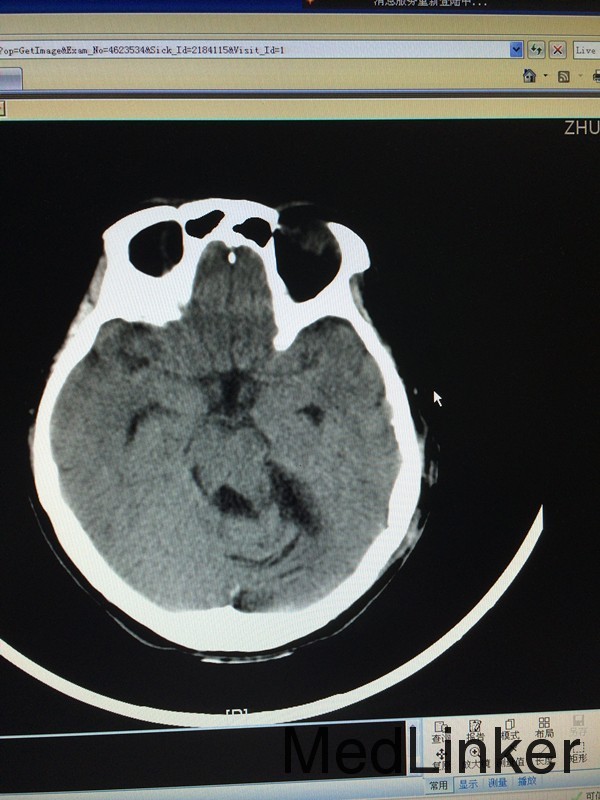

查体:左侧轻微面瘫,左侧面部感觉稍减退,余无特殊 辅助检查:头颅CT提示左侧桥小脑角区类圆形肿物,考虑听神经瘤可能,四脑室受压变窄并右移

诊断:左侧听神经瘤 治疗:行左侧桥小脑角区占位切除术,术后病理提示左侧桥小脑角神经鞘瘤